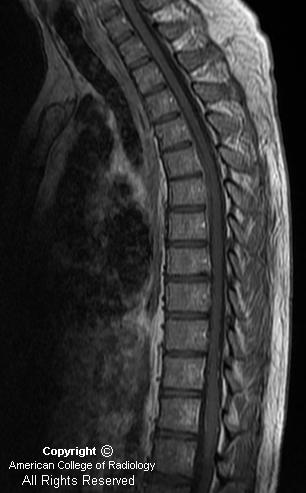

A sagittal T2 weighted MR of the thoracic spine demonstrates a fluid collection in the ventral epidural space from T2-T3 to T7-T8. This collection is iso-to hyperintense on T1 weighted sequences, and hypointense on T2 weighted sequences, consistent with recent hemorrhage.

Diagnosis: Spontaneous Spinal Epidural Hematoma with Evidence of Active Extravasation